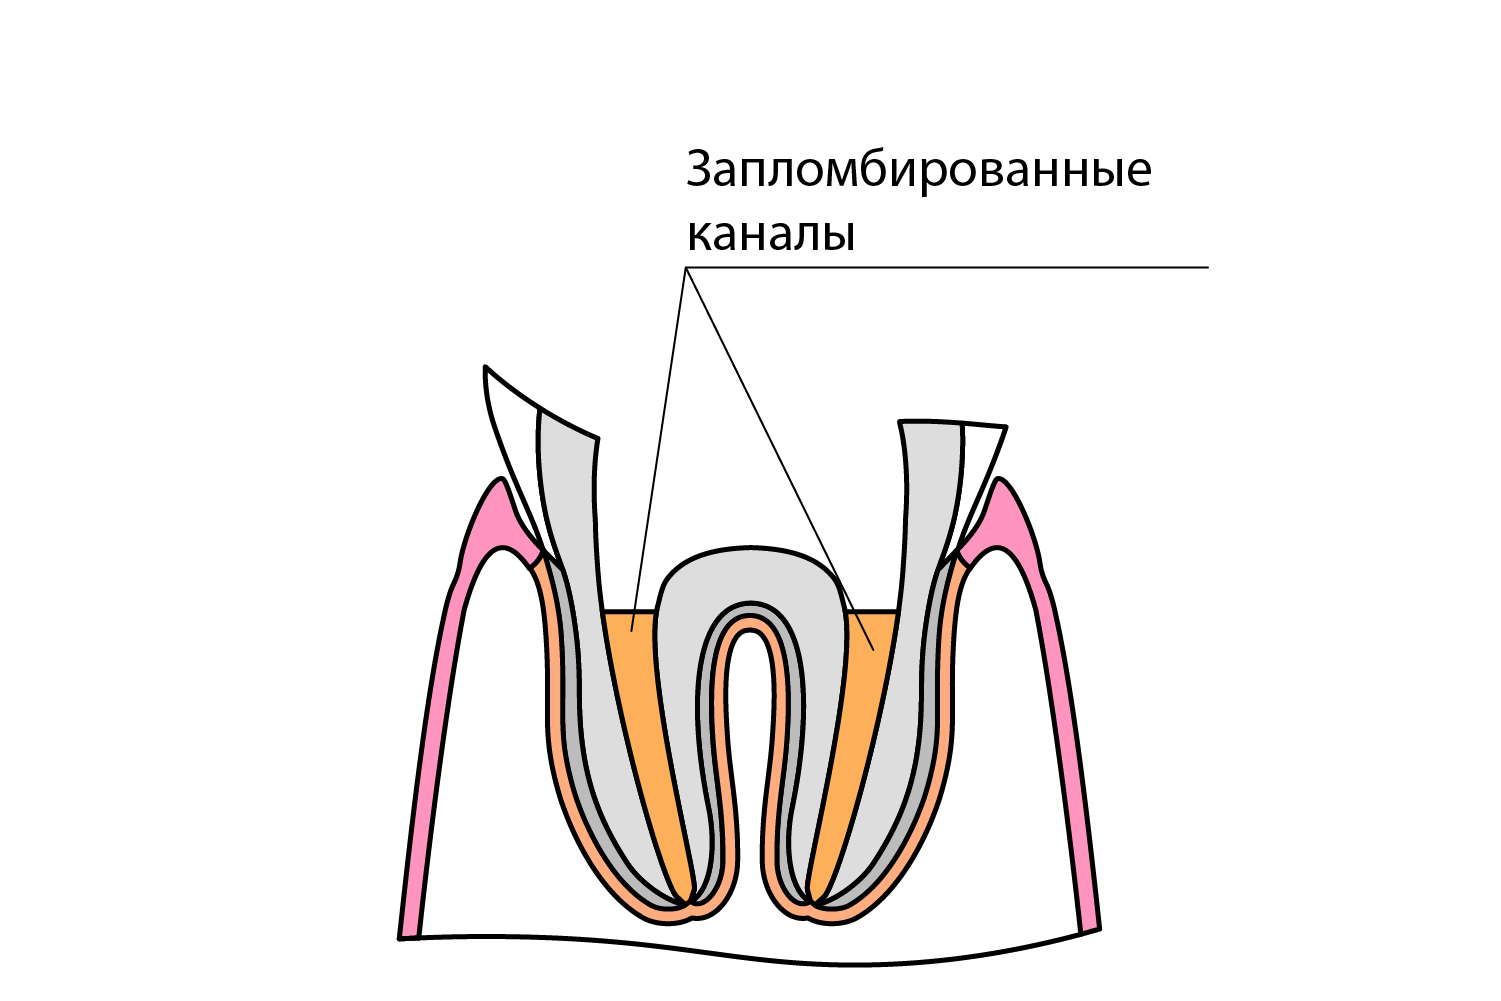

Культя зуба это

Культя зуба это 106 фото